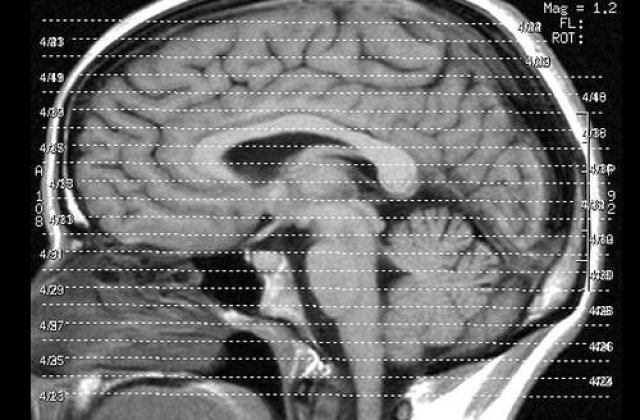

Reprimarea indelungata a amintirilor rele poate duce la stergerea lor complete, sustin cercetatorii. Acestia au folosit scanari EEG pentru a monitoriza partile din creier care se activeaza atunci cand cineva incearca sa uite ceva. – Acestia au putut spune chiar si momentul in care amintirea este uitata si sustin ca reprimarea indelungata este la un pas distant de stergerea complete.